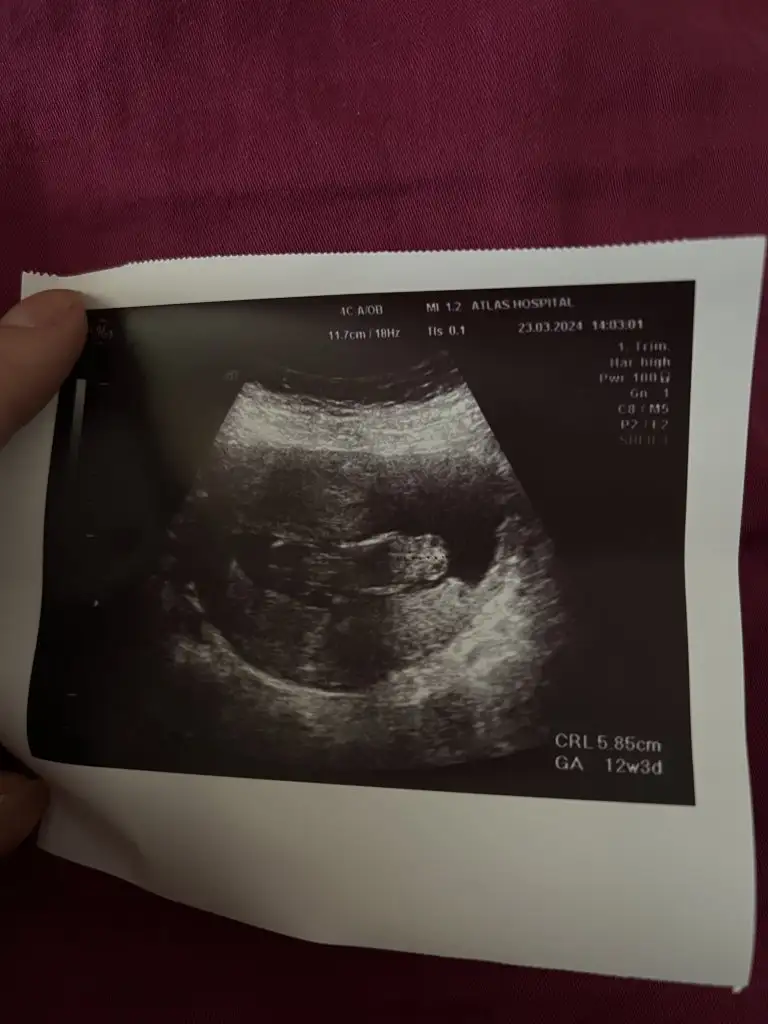

Banada bakarmısın 11+4 karından ultrasonKızlar bebişlerinizin ultrason resimlerini ve cinsiyetini kaçıncı haftada olduklarını yazında kendi ultrason resimlerimizle kıyaslayıp fikirde bulunalım. Nub teorisi, kafa şekli, kemik yapısından cinsiyet teorileri tutuyor mu bakalım bir

Evet canım hala erkek geliyo bana sırtını dönmüş ama başka var mı düzgünEki Görüntüle 3393072